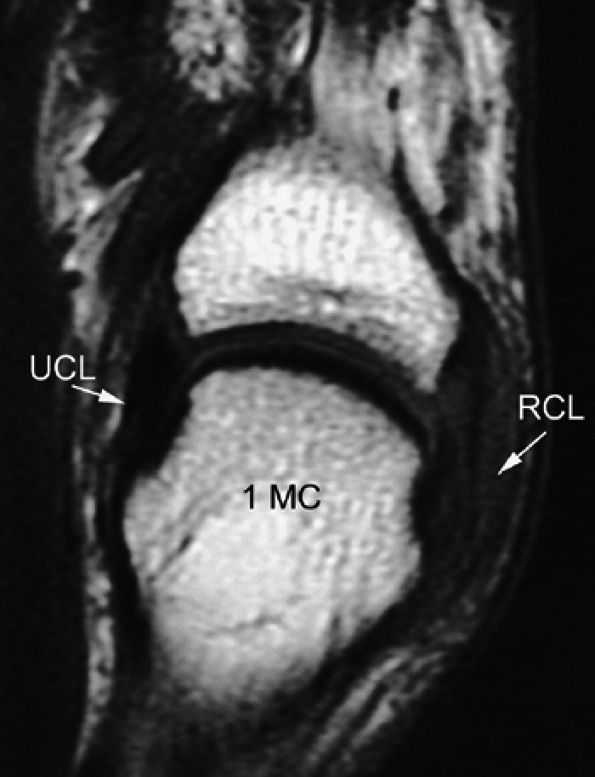

The collateral ligaments are taut and visible all along their course (Fig. 11.12).28,29,30,31

Stress imaging also allows assessment of the stability of the extensor tendon.28 When injured, the ligament appears thickened all along its course, but the presence of fluid in a tear is uncommon in chronic lesions.